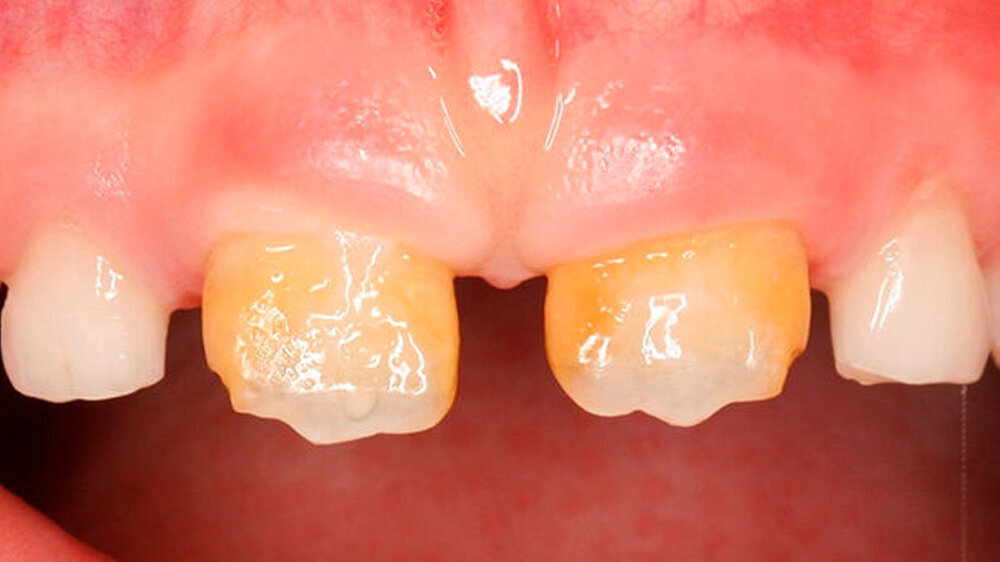

Mit dem Durchbruch der ersten bleibenden Molaren treten dann bisher unbekannte Beschwerden auf wie zum Beispiel eine übermäßig ausgeprägte Kälte-/Wärmeempfindlichkeit. Für manche Kinder wird dadurch nicht nur die Mundhygiene sondern auch die Nahrungsaufnahme erschwert. Zusätzlich bricht oft schon in der Durchbruchs-Phase der Schmelz ein (Abbildung 1), was die Überempfindlichkeit in teils akute Zahnschmerzen übergehen lässt.

Das klinische Bild der MIH reicht von einem bis zu vier betroffenen Molaren, nur selten sind alle Zähne in ähnlicher Ausprägung geschädigt [Weerheijm et al., 2001]. Die bleibenden Frontzähne können ebenfalls betroffen sein, diese weisen allerdings in der Regel keinen Schmelzeinbruch auf und sind selten bis gar nicht überempfindlich [Weerheijm et al., 2001] (Abbildung 2).

In schwerwiegenden Fällen kann der Einsatz eines Komposits das beste Ergebnis erzielen (Abbildungen 2, 13 und 14)